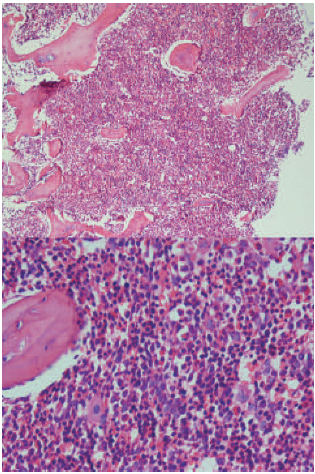

Bone marrow aspiration and trephine biopsy were performed to rule out posttransplant lymphoproliferative disorder. The results showed normal cellular marrow with increased numbers of megakaryocytes in favor of ITP (Figure 1). The results of bone marrow flow cytometry indicated the presence of 2% of immature myeloid cells and about 4% of hematogones, which was not suggestive of malignancy. With the possibility of ITP, daily methylprednisolone (30 mg/kg) was given for 3 consecutive days. Despite methylprednisolone therapy, the patient’s platelet count was still extremely low (2 × 109/L). Because the patient’s platelet count was critically low, this was considered as an emergency situation. Therefore, daily IVIG (1 g/kg) for 2 days was immediately given. The patient’s platelet count rose slightly but without dramatic response, showing a level of 7 × 109/L (14 days after start of bleeding symptoms).

Figure 1. Bone Marrow Aspiration and Trephine Biopsy